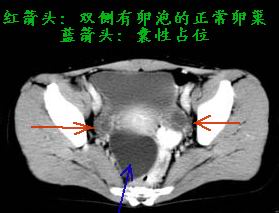

我来帮你解释:

【首先先分清解剖,见下图,双侧卵巢正常存在,无占位,子宫直肠凹囊性占位与双侧卵巢均无联系,因此不是卵巢发生的囊性占位】

【再看我的课件的一部分内容】

仔细阅读,你会发现假性囊肿可以忽大忽小,甚至消失,为腹腔内渗出的结果,形态却像囊肿。

回答你三个疑问:

1、囊肿位于腹膜腔。

2、肯定不是来源卵巢(双侧可见正常卵巢),腹腔镜探查子宫卵巢当然没有问题。

3、并非卵巢囊肿破裂,而是假性囊肿所致。

包裹性积液也是一种假性囊肿,见下图